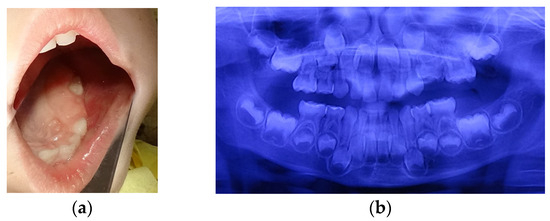

At the age of 5 y and 3 m, a molar erupted in the left upper arch. The erupting tooth was considered to be the second primary molar (65), although its shape and size, as seen on the new panoramic X-ray, substantially differed from those of 55, present on the arch. This new X-ray also suggested that 64 could be mechanically impacted by 63 (Figure 2a,b).

Figure 2.

Age of 5 y and 3 m. (a) Occlusal view of the left upper arch; (b) panoramic X-ray.